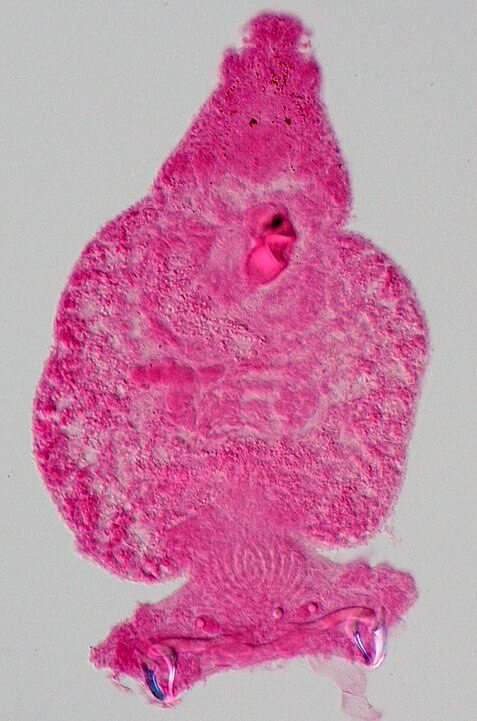

- Trematoda. Son las famosas “duelas”, parásitos de reducido tamaño, en comparación con otros platelmintos. Su cuerpo también está cubierto por una cutícula protectora, pero no está dividido en segmentos ni zonas. Además presentan dos ventosas, una a nivel ventral y la otra en el área oral. Entre las especies más representativas de esta clase se encuentran: Fasciola hepática, Schistosoma mansoni y Schistosoma mekongi, entre otros conocidos patógenos del ser humano.

- Monogenea. Comprende un total de 1.000 especies, aproximadamente. Está constituido por ectoparásitos que normalmente se fijan al cuerpo de vertebrados como peces, reptiles y anfibios. Son parásitos muy pequeños, pues apenas alcanzan los 2 cm. Su cuerpo, cubierto de cutícula protectora, no está dividido. Presentan órganos de fijación, principalmente ventosas, aunque también pueden presentar ganchos, con los que se fijan y mantienen unidos al cuerpo de sus hospedadores. Los monogéneos no parasitan al ser humano.